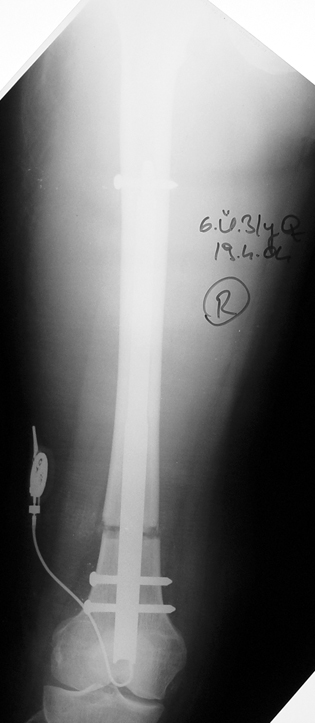

Tamamen vücut içerisinde kalan bir donanıma sahip, dereceli olarak iki kemik arasında uzatma yapabilmektedir. Üstün teknik altyapısı sayesinde, çivi telemetrik olarak kumanda edilmekte ve hiçbir dış bağlantıya ihtiyaç duymamaktadır.

Hastanın enfeksiyon riskini azalttığı gibi, daha az ağrı duymasını da sağlar ve kozmetik sıkıntılar oluşturmaz. Hastanın daha kısa sürede günlük yaşamına dönmesine ve hastanede de daha az kalması bu teknikle mümkündür. Femur, tibia ve humerus için farklı tipleri vardır.